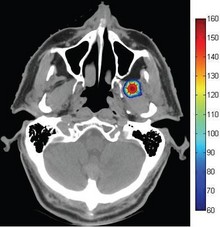

The Eustachian Tube (ET) is a collapsible tube that connects the middle ear to the nasopharynx. Dysfunction ...扩展阅读